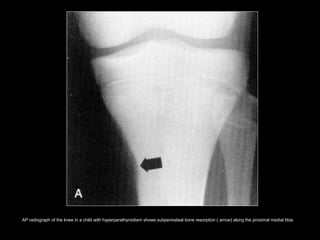

AP radiograph of the knee in a child with hyperparathyroidism shows subperiosteal bone resorption ( arrow) along the proximal medial tibia.

AP radiograph ofthe knee in a child with hyperparathyroidism shows subperiosteal bone resorption ( arrow) along the proximal medial tibia.